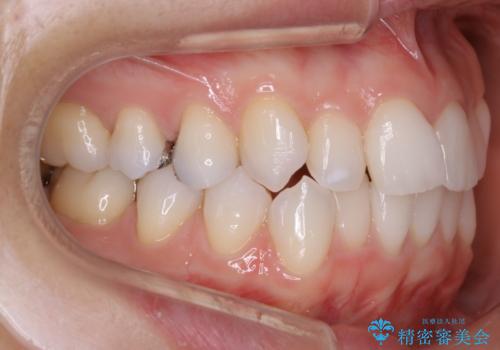

歯並びが悪くなる原因の一つに「歯列弓の狭窄」というものがあります。

奥歯や前歯が内側(舌側)に倒れ込んでしまったり、歯が生えてくる位置が内側になってしまうことにより歯並びのアーチが狭くなってしまうことを言います。

このような場合、歯並びのアーチを拡大してあげるだけでもガタつきを無くすためのスペースがかなり作れることがあります。